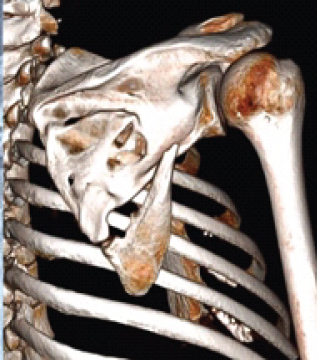

3D-Assisted Scapular Fracture Fixation in a Polytraumatized Patient: A Case Report

Jordan Dobrich , Michael K Deegan , Caleb D Gerber , Kyong S Min

………………………………p.123-127